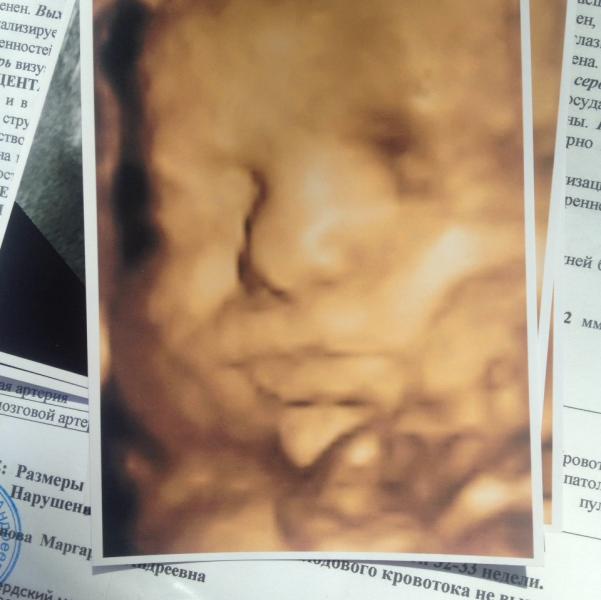

Наш Лучок. Срок 30-31 по узи 32-33. Пдр 2.08 по узи 21.07. Вес на данный момент 1780, ждать 4100 сказали.... Охохох. Дочка 3900 родилась